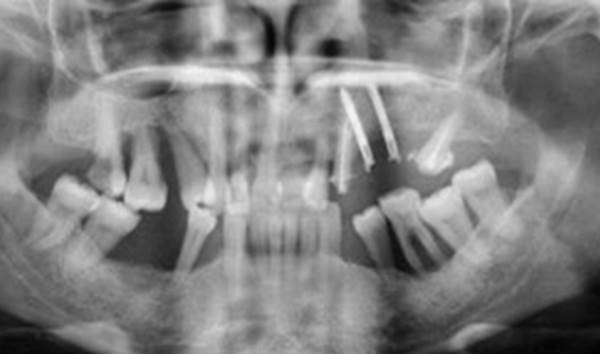

Clinical case: Extraction of all teeth in upper maxilla,

immediate implant placement, & provisionalization

- Courtesy of Dr. Iulian Filipov, Romania -

Keywords

AnyRidge, immediate placement, immediate provisionalization, maxillary fully edentulous case, initial stability, edentulous, Dr. Iulian Filipov, R2GATE, MEGA ISQ

Products:

AnyRidge implant system, Mega ISQ, R2GATE

“AnyRidge ensures long-term biological stability

& functionality even in

full-mouth rehabilitation case. ”